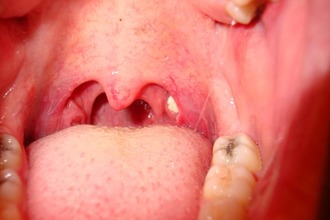

Паратонзиллит

Паратонзиллит (паратонзиллярный абсцесс) — это инфекционное заболевание, поражающее околоминдаликовую клетку и сопровождающееся значительным отеком лимфоидных тканей. Абсцесс может быть как односторонним, так и двусторонним и формируется в результате септического воспалительного процесса в миндалинах и окружающих их тканях. Наиболее уязвимыми к этой патологии являются маленькие дети и пожилые люди из-за снижения иммунной реакции организма.

Если боль в миндалинах сохраняется длительное время, это может привести к распространению патологических процессов и затруднению дыхания. О развитии паратонзиллита могут свидетельствовать следующие симптомы:

- высокая температура (выше 39°);

- увеличение лимфатических узлов;

- затрудненное дыхание;

- спазмы жевательных мышц;

- увеличение миндалин;

- усиливающаяся боль при глотании;

- общая слабость и тошнота.